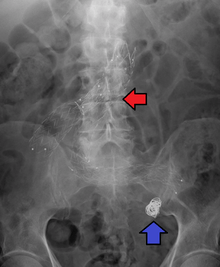

Fusiform aneurysms ("spindle-shaped" aneurysms) are variable in both their diameter and length; their diameters can extend up to 20 cm (8 in). They often involve large portions of the ascending and transverse aortic arch, the abdominal aorta, or less frequently the iliac arteries.[3]:357

- The aorta, namely aortic aneurysms including thoracic aortic aneurysms and abdominal aortic aneurysms.

For aneurysms in the aorta, arms, legs, or head, the weakened section of the vessel may be replaced by a bypass graft that is sutured at the vascular stumps. Instead of sewing, the graft tube ends, made rigid and expandable by nitinol wireframe, can be easily inserted in its reduced diameter into the vascular stumps and then expanded up to the most appropriate diameter and permanently fixed there by external ligature.[24][25] New devices were recently developed to substitute the external ligature by expandable ring allowing use in acute ascending aorta dissection, providing airtight (i.e. not dependent on the coagulation integrity), easy and quick anastomosis extended to the arch concavity[26][27][28] Less invasive endovascular techniques allow covered metallic stent grafts to be inserted through the arteries of the leg and deployed across the aneurysm.